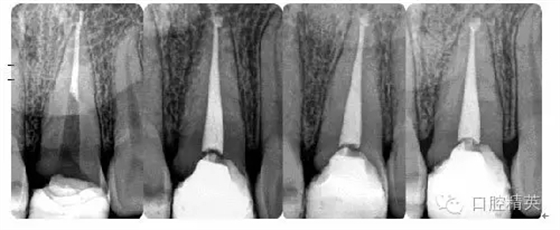

病例6:折斷器械取出

病例7:根尖切除術

病例8:牙周植骨術